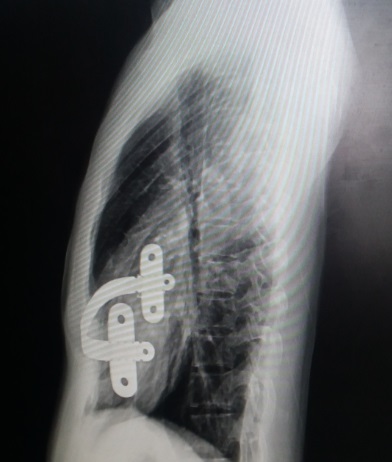

术前行X线检查:正位片提示胸壁内有钢板一条,钢板位置倾斜,脊柱轻度侧弯(图4)。侧位片提示前胸壁下部局部凹陷,钢板位置偏斜(图5)。行CT检查:可见胸壁内钢板影。横截面未见明显凹陷,但不同水平前后径明显不同(图6-10)。三维重建提示钢板影,前胸壁凹陷畸形(图11,12,13)。心电图及腹部超声检查未发现异常。

图5,X线检查:侧位片提示前胸壁下部局部凹陷,钢板位置偏斜。